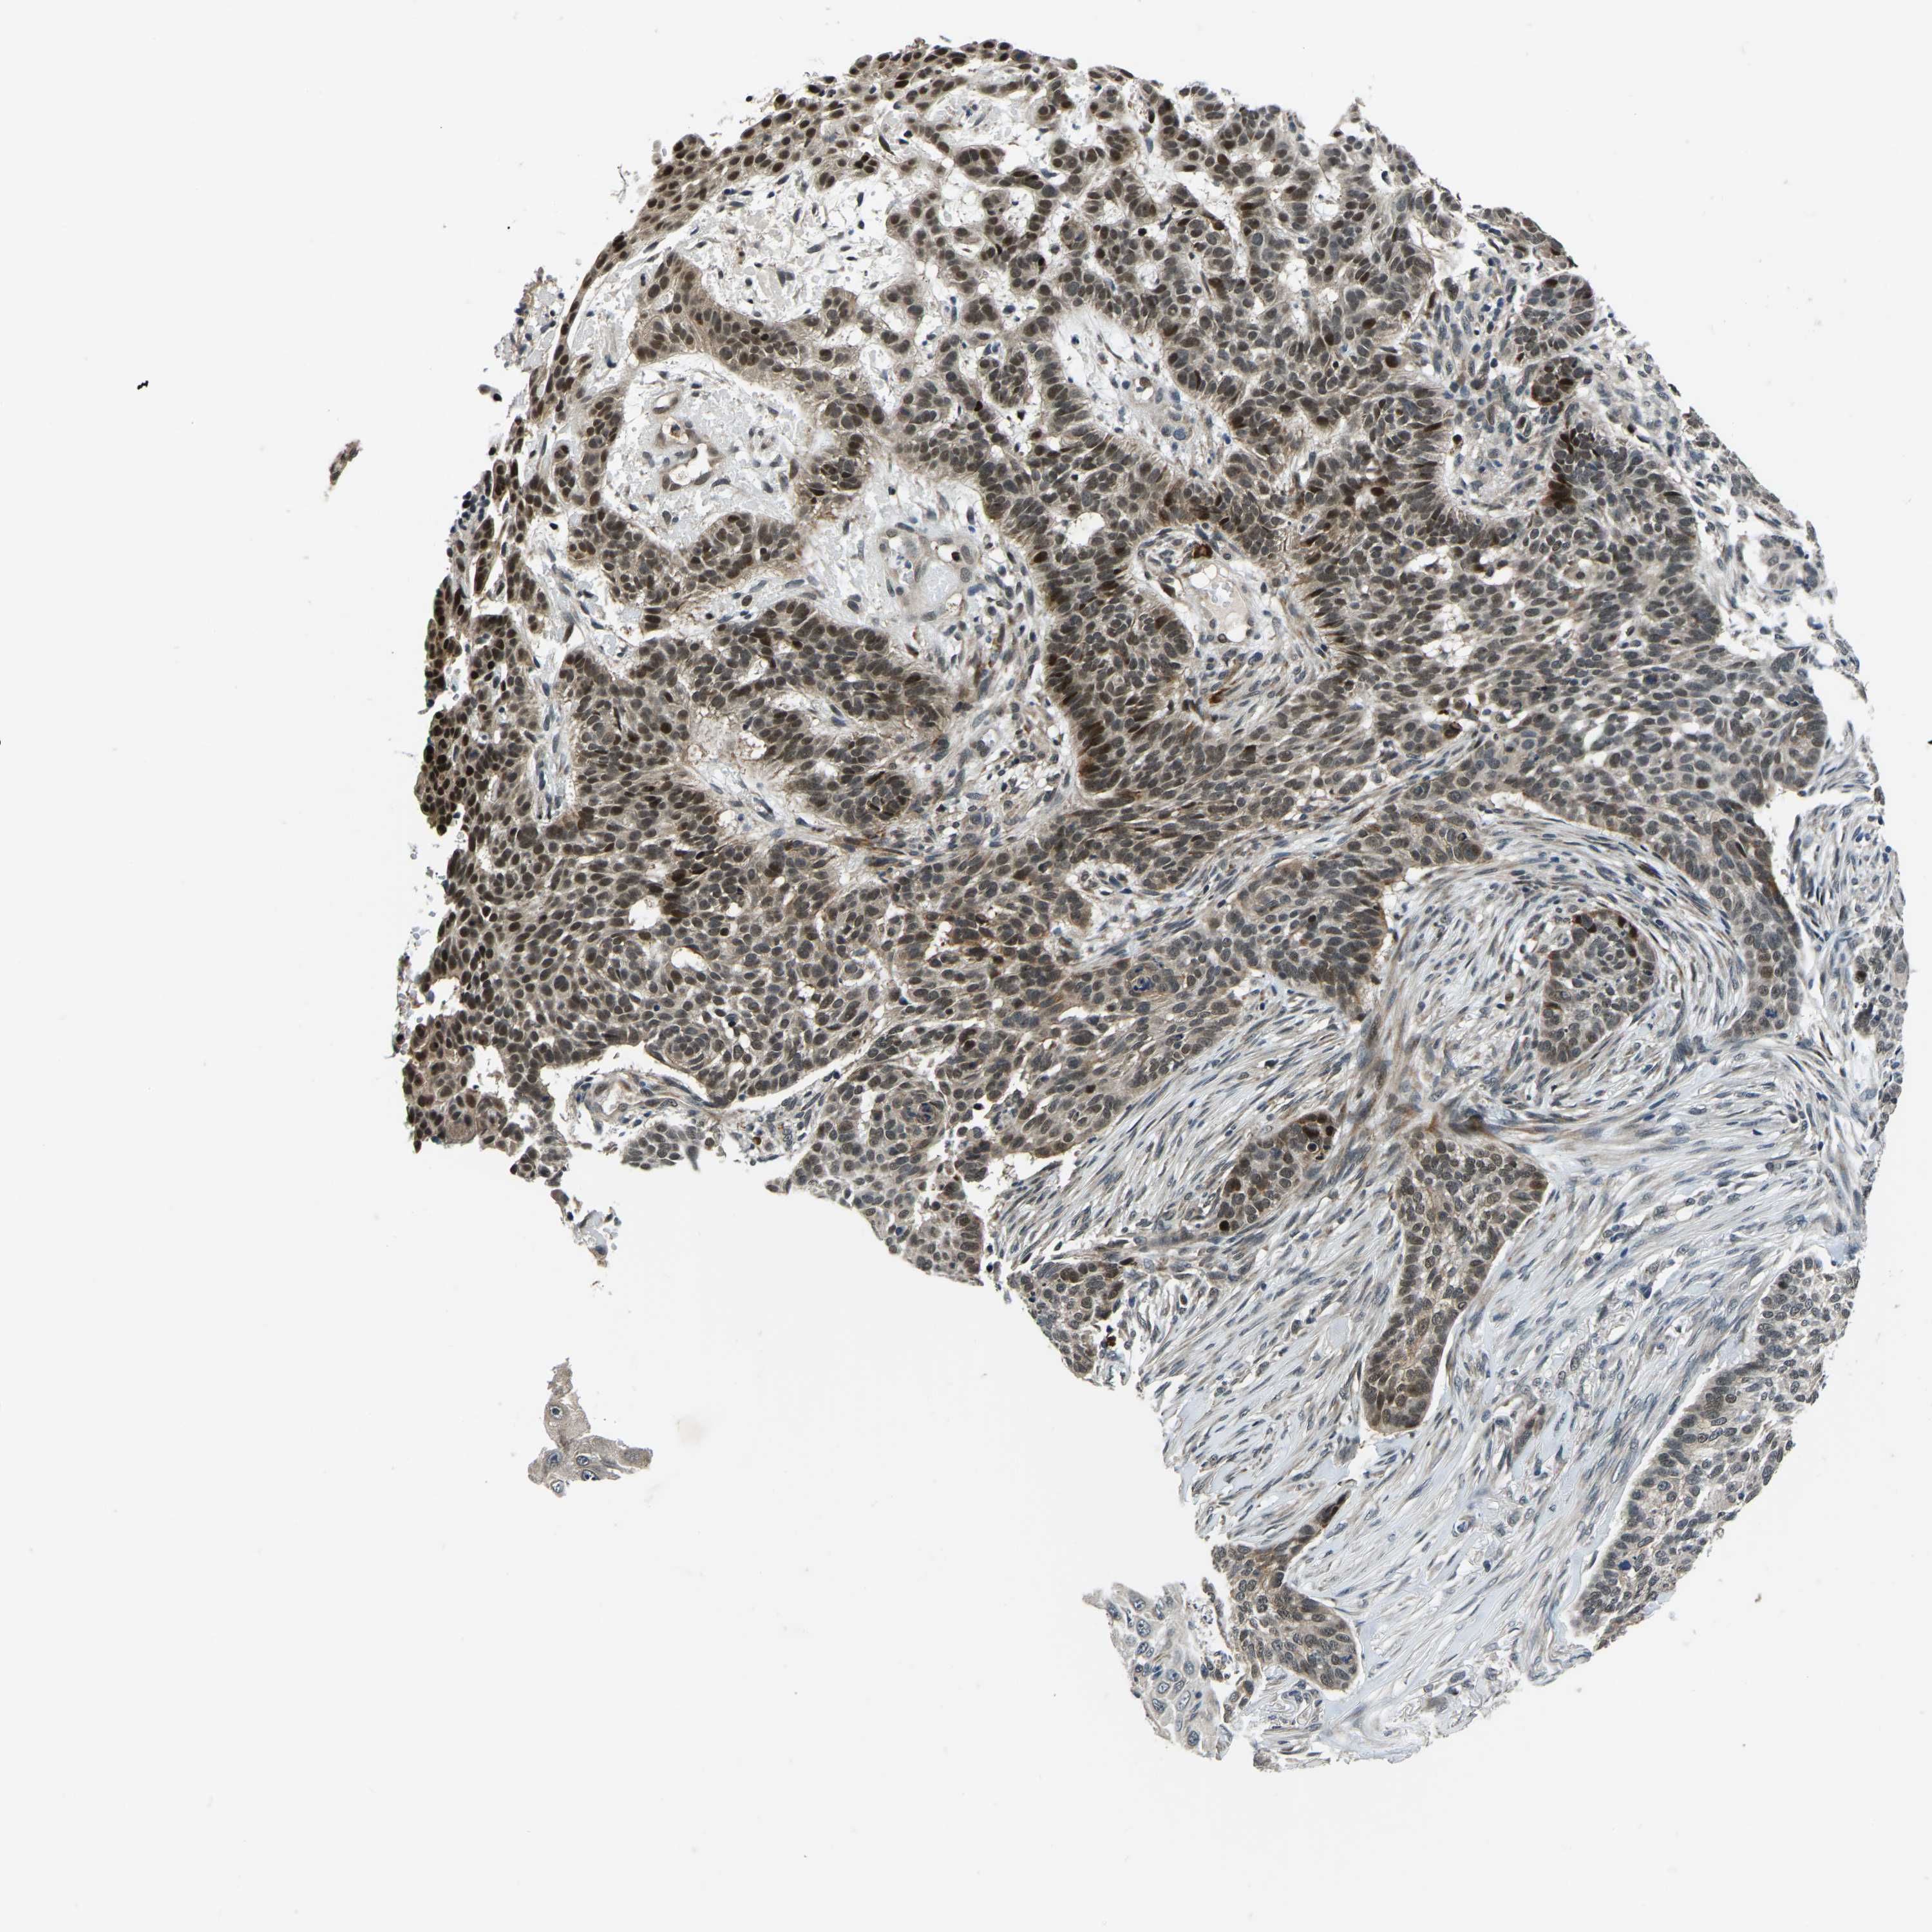

SKIN CANCER - Protein expressioni

A mouse-over function shows sample information and annotation data. Click on an image to view it in a full screen mode. Samples can be filtered based on level of antibody staining by selecting one or several of the following categories: high, medium, low and not detected. The assay and annotation is described here.

Antibody stainingi

Antibody staining in the annotated cell types in the current human tissue is reported as not detected, low, medium, or high, based on conventional immunohistochemistry profiling in selected tissues. This score is based on the combination of the staining intensity and fraction of stained cells.

Each image is clickable and will lead to virtual microscopy that enables deeper exploration of all samples and also displays staining intensity scores, fraction scores and subcellular localization as well as patient and tissue information for each sample.

Antibody HPA019486

Antibody HPA021517

Staining

High

Medium

Low

Not detected

Intensity

Strong

Moderate

Weak

Negative

Quantity

>75%

75%-25%

<25%

None

Location

Nuclear

Cytoplasmic/membranous

Cytoplasmic/membranous,nuclear

Basal cell carcinoma

Squamous cell carcinoma, NOS

Squamous cell carcinoma, metastatic, NOS